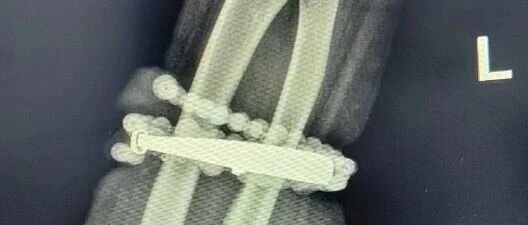

然而,就在兩周前,龔女士的情況急轉(zhuǎn)直下:手腕不僅疼痛加劇,還出現(xiàn)了明顯的紅腫,甚至有膿液滲出。她這才驚覺(jué)——手鐲和串珠,已經(jīng)有一部分“長(zhǎng)”進(jìn)了肉里,根本取不下來(lái)了!

“這是典型的首飾長(zhǎng)期壓迫、摩擦,加上細(xì)菌感染,引發(fā)的慢性炎癥和肉芽組織增生?!贬t(yī)生介紹,此時(shí),手鐲和串珠已經(jīng)成了一個(gè)不斷刺激皮膚、污染傷口的“病灶”,如果不盡快手術(shù)取出,感染可能進(jìn)一步擴(kuò)散,甚至危及生命或影響手臂功能。

經(jīng)過(guò)一個(gè)多小時(shí)的手術(shù),醫(yī)生們將手鐲和串珠從厚厚的增生組織中完整剝離出來(lái)。目前,龔女士恢復(fù)良好,已順利出院。